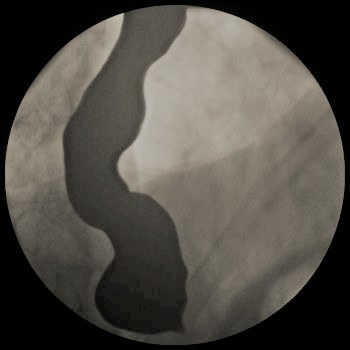

Figure 2. Patient’s chest x-ray.

A 72-year-old gentleman with achalasia who weighed 91 kg was admitted for an elective POEM procedure (Figure 1). The procedure started with stable hemodynamics on a constant ventilator setting of respiratory rate of 10-16/hr; tidal volume of 443; positive end-expiratory pressure (PEEP) of 5 cm H2O; positive inspiratory pressure of 22-24; end tidal carbon dioxide of 28; arterial oxygen saturation of 100. However, 45 minutes into the procedure, the patient went into pulseless electrical arrest. The scope was withdrawn, and he was revived after 10 minutes of cardiopulmonary resuscitation. The procedure was aborted and he was transferred to the ICU intubated, critically ill, and on escalating doses of epinephrine and norepinephrine. Follow-up diagnostic imaging (Figures 2 and 3) showed a small heart with air tracking around it, the mediastinum, the esophagus, and the aorta, confirming tension pneumomediastinum.

Figure 3. Patient’s CT scan.